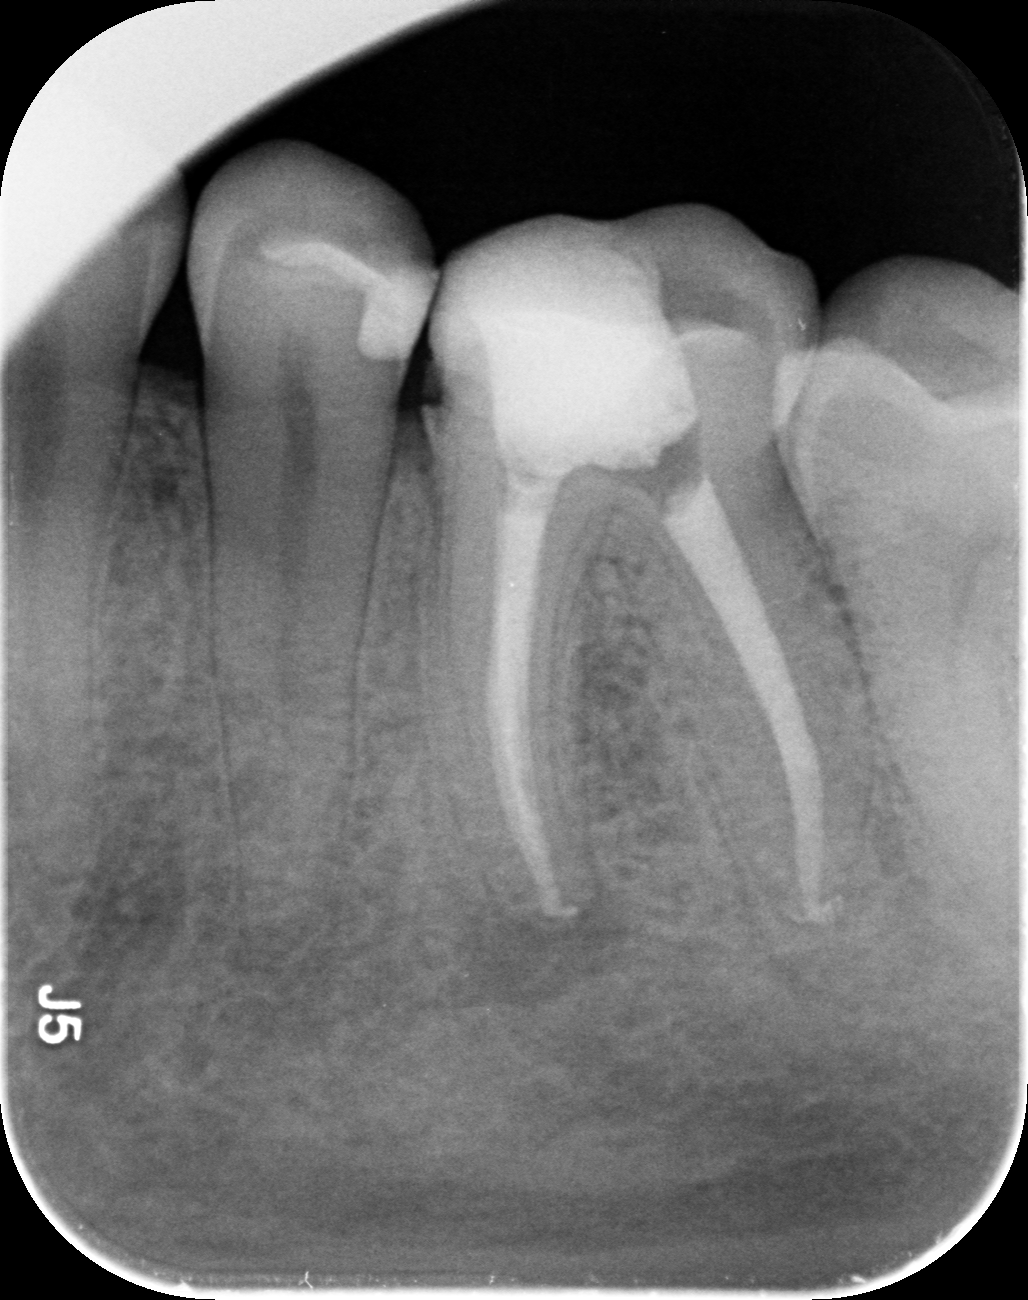

Dantų kanalų gydymas